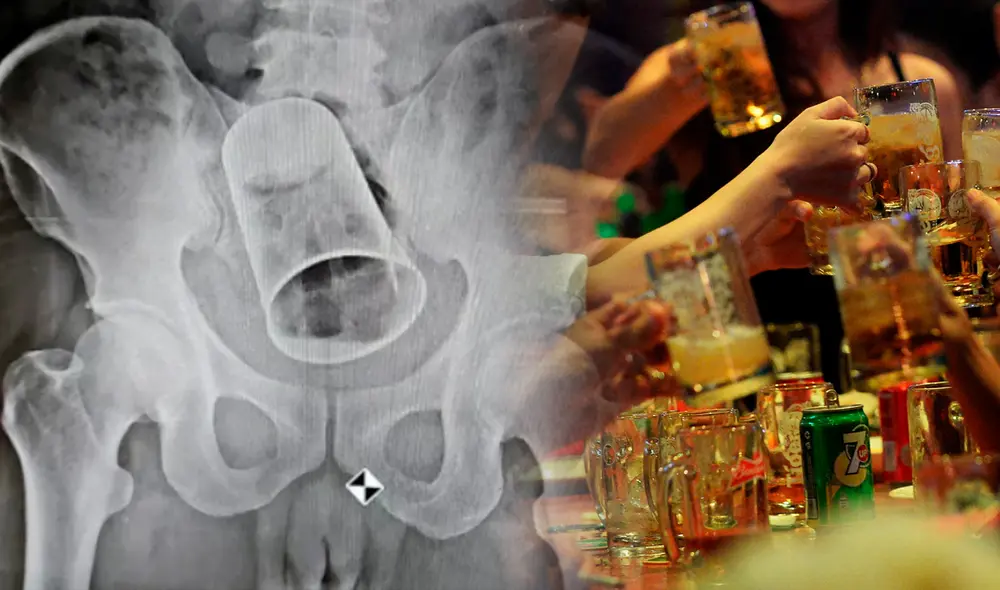

Un hombre de 45 años de edad fue salvado por un grupo de médicos en un hospital ubicado en Balipadar, India, tras acudir a emergencias por tener una copa de metal dentro del recto. Según el afectado, tenía el objeto insertado desde hace 10 días, pero le daba vergüenza solicitar ayuda.

La pieza metálica de un tamaño considerable estaba bloqueando la salida de las heces, por lo que el sujeto tuvo que ser operado de urgencia por una obstrucción intestinal y por poseer el estómago inflamado, según un portal web local.

Sin embargo, dicha intervención, realizada el último 19 de agosto, fue un éxito. Por su parte, el sujeto narró que la copa de metal, de ocho centímetros de diámetro y 15 de largo, acabó dentro de su ano cuando se encontraba en una fiesta con sus amistades.

Con el objetivo de jugarle una broma, sus propios amigos fueron quienes se lo metieron cuando la víctima se encontraba en estado de ebriedad. No obstante, el hombre terminó por sacarse una radiografía que mostró la copa obstruida en su intestino.

En plena operación, los cirujanos tuvieron que cortar el intestino con el fin de sacar el objeto de metal. Por otro lado, fue la familia del hombre que lo llevó de urgencia al centro médico, luego de que este confesara lo que le había pasado. Según los especialistas, notaron que el paciente estaba grave de salud y que puso en riesgo su vida.